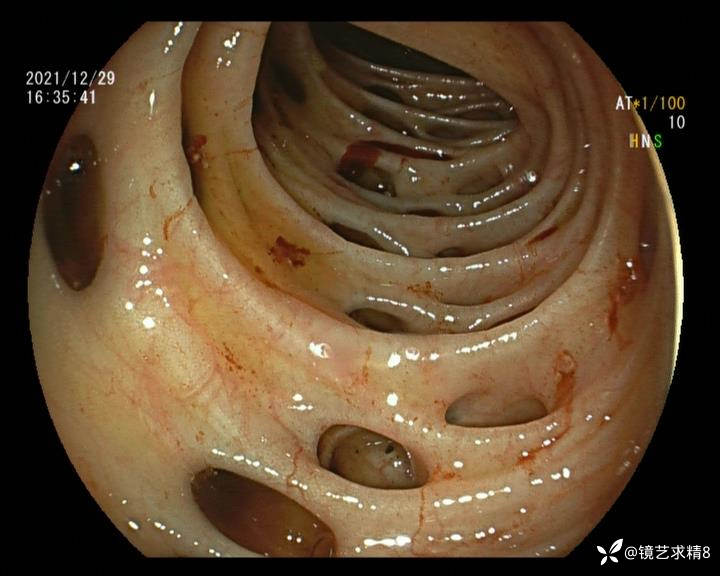

患者以消化道出血入院,胃镜未见异常,肠镜进入乙状结肠就看到很多憩室,同时还看到肠腔用清肠药后移动下来1枚尖锐的枣核,这么多憩室,这个枣核扎入憩室的机会非常大,推测应该是掉入一坑🕳就算出来还会有很多坑🕳🕳🕳等着,掉入憩室内很容易刺破血管,这可能就是消化道出血的原因,继续前进可以看到有一些憩室内翻,还有一些息肉,问题来了,那么多憩室,犯罪分子是抓住了,它在那些憩室内作过案?到达回盲部后挨个冲洗,但憩室大小又不足以把镜头进入憩室内观察,针对有血块的憩室冲洗后可疑出血的以夹子闭合或套扎,取出枣核,如果有锥形透明帽可能钻入憩室精准电凝效果更好,若内镜下操作失败介入治疗成功率更高,经内镜下治疗后观察未再出血出院。

亚洲人群结肠憩室主要发生在右半结肠,然后随着年龄的增长而延伸到左半结肠和双侧结肠。相比之下,欧美人群80%的结肠憩室好发于左半结肠,其中乙状结肠憩室占 70%,而大多是假性憩室。 然而,与憩室炎主要发生在左半结肠不同,东西方人群的憩室出血均主要发生在右半结肠,可能与右半结肠的憩室更宽大及憩室血管更易受到损伤相关。

如何诊断憩室出血是临床面临的第一个难题,因为上消化道出血的发生率较高,常规便血患者需要排出上消化道出血的因素,进而进一步确认是否进行肠镜检查。憩室出血具有自发性停止的特点,往往骤起骤停,在出血间期或患者出现休克血压时结肠镜检查通常不能捕捉到近期憩室出血的表现。对于怀疑憩室出血的患者,往往需要更有耐心地反复冲洗观察,从而确认罪犯憩室。